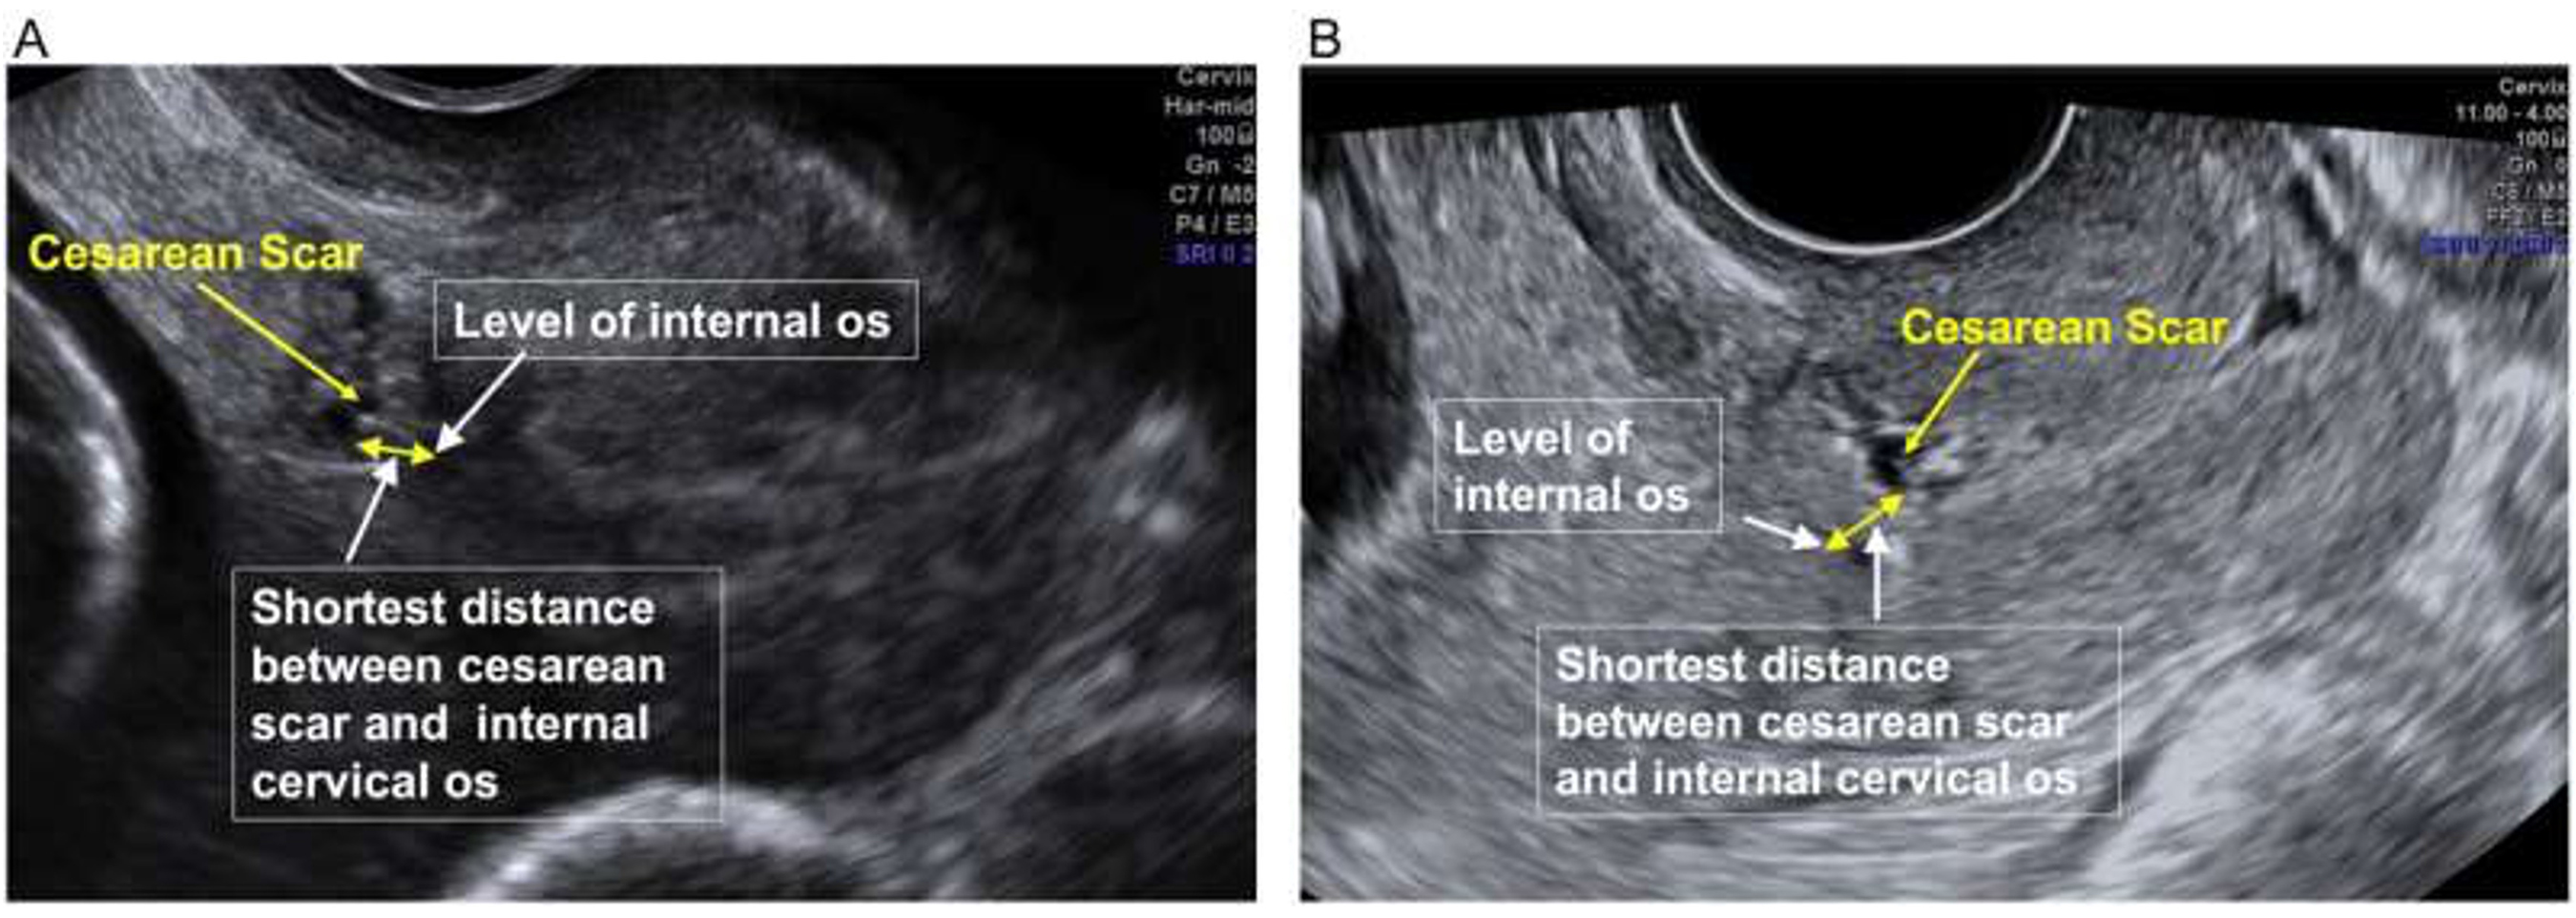

The team used a validated transvaginal ultrasound technique—which they developed in 2022—to assess the position of the womens C-section scar in relation to their cervix (neck of the womb).

An ultrasound probe was inserted into the vagina and gently moved on either side to assess the cervical length and the height of C-section scar.

If researchers were unable to see a C-section scar, then they found that the women were unlikely to have a preterm birth.

However, if the scar was low down the womb or within the cervix then there was a much higher chance of the cervix becoming short in mid-pregnancy and of women then delivering preterm.